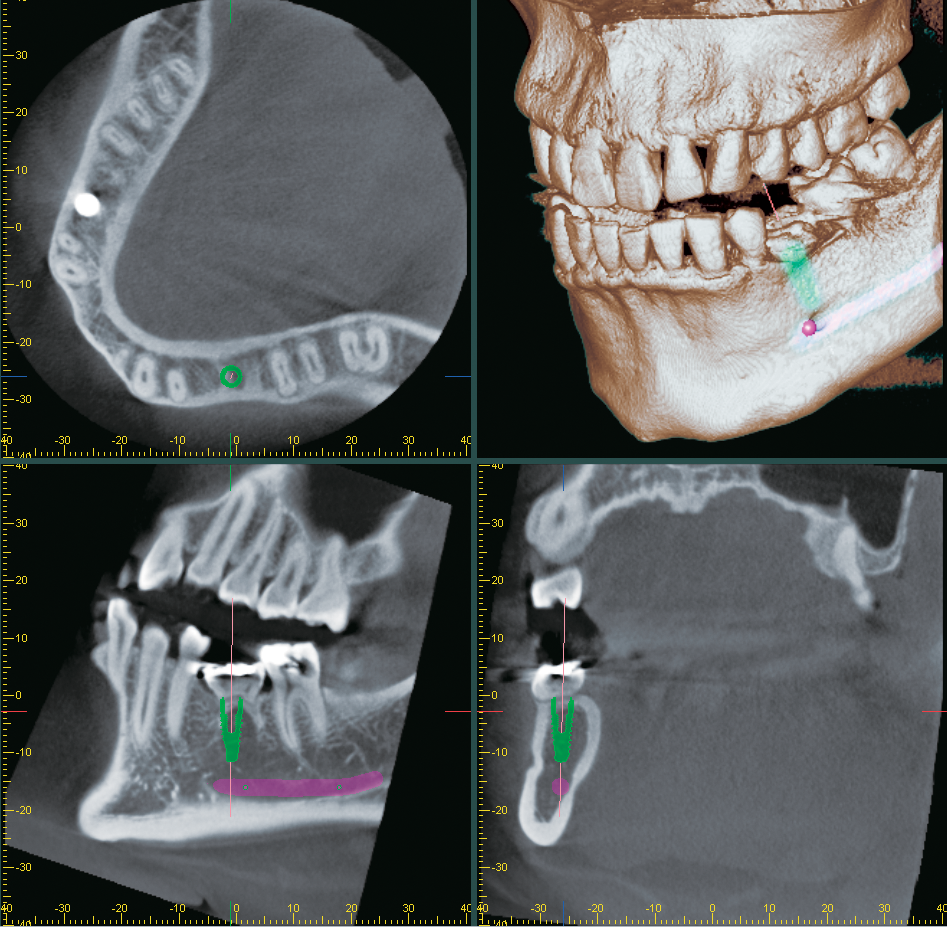

Carestream Dental’s latest addition to the SMOP implant planning system is an easy, versatile stackable guide solution for use with full-arch implant restorations. The stackable guide can be designed from a single workflow, and the templates easily lock together for user-friendly chairside use. It is ideal for the immediate loading of provisionals. With the new stackable guide technology, a comprehensive digital 3D design process is used to create an efficient and reliable solution for complex procedures. Through cloud-based planning and design, the interlocking fit of the stackable guide ensures optimal patient outcomes.

3D Diagnostix Digital Services will now be integrated with J. Morita USA’s i-Dixel imaging software. The integration allows i-Dixel imaging software users to order digital services from 3D Diagnostix, including radiology reports, implant treatment plans, computer-guided surgery solutions, and Magnetix™ guided full-mouth restorations. This partnership also allows users to order digital design services for in-office 3D printing of surgical guides and prosthetics.

The DS OmniTaper Implant System is a new solution for implant treatment designed for virtually all clinical situations. The OmniTaper EV Implant features ActiveBone Control design and has an apically tapered shape. The ActiveBone Control design uses a combination of bone-specific preparation protocols and the dual-core bone condensing thread design to achieve high primary stability. This combination is said to ensure safe and atraumatic implant placement, even in soft bone. The conical EV connection ensures a tight, stable fit and minimizes micromovement and microleakage. Additionally, it provides access to the EV prosthetic range for restorative flexibility and offers clinicians efficiency for immediate chairside solutions. The DS OmniTaper Implant System is slated for release in early 2023.